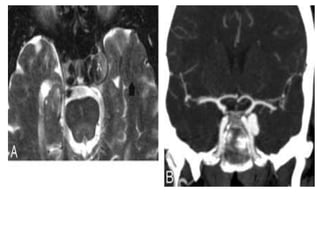

• #13 CS thrombosis. A, Coronal post contrast T1-weighted image shows an enlarged and inhomogeneous-appearing right CS that contains areas of low signal intensity (arrow) compatible with clot. B, Coronal post contrast T1-weighted image in a different patient shows a large nonenhancing clot expanding the left CS. The ipsilateral ICA is slightly narrowed.